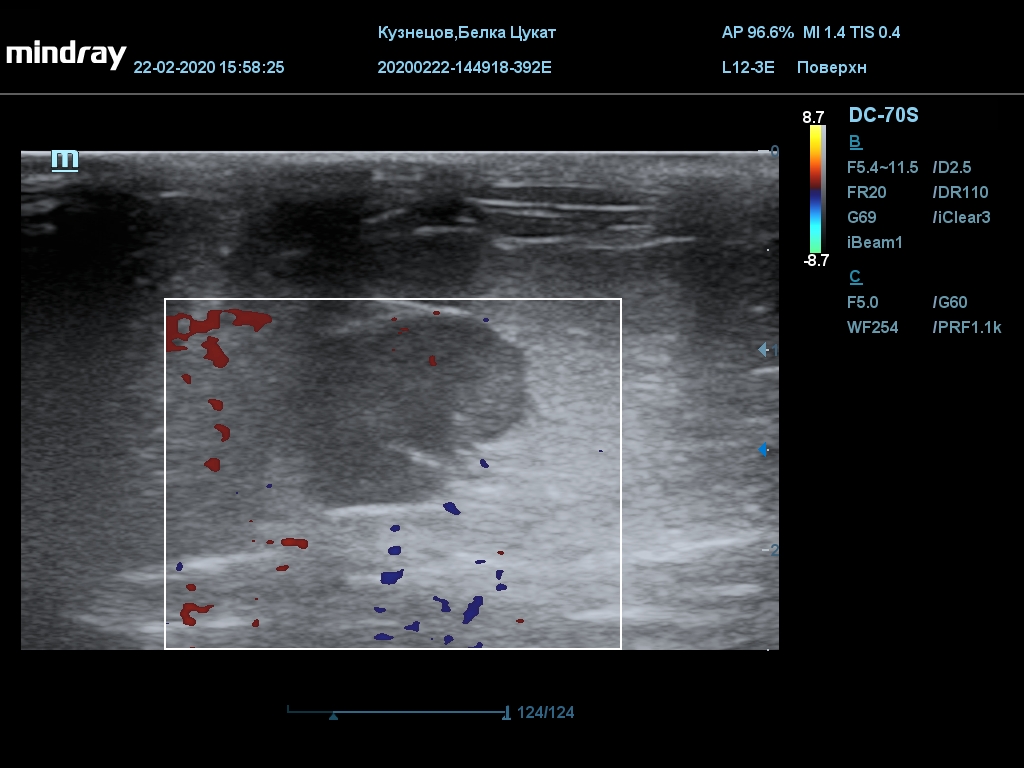

УЗИ

(почки, мочевой пузырь и, предположительно, простата)

Обращаю внимание, что делала УЗИ и писала заключение узист, которая специализируется на кошках и собаках, поэтому она сделала узи и описала, как смогла, но тонкостей грызунячьей анатомии она не знает.

Приложил только фото, есть ещё пара видео, но не знаю, как тут выложить, и надо ли.

Каудальнее мочевого пузыря визуализируется округлая структура размером 11,1 х 8,3 мм с ровными контурами гипоэхогенная однородная, с признаками васкуляризации.

Заключение: УЗпризнаки уролитиаза, объёмная структура каудальнее мочевого пузыря. Признаки расширения левой лоханки.

УЗИ

(почки, мочевой пузырь и, предположительно, простата)

Обращаю внимание, что делала УЗИ и писала заключение узист, которая специализируется на кошках и собаках, поэтому она сделала узи и описала, как смогла, но тонкостей грызунячьей анатомии она не знает.

Каудальнее мочевого пузыря визуализируется округлая структура размером 11,1 х 8,3 мм с ровными контурами гипоэхогенная однородная, с признаками васкуляризации.

Заключение: УЗпризнаки уролитиаза, объёмная структура каудальнее мочевого пузыря. Признаки расширения левой лоханки.